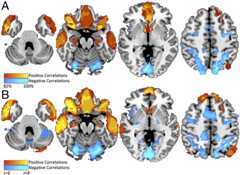

The set of regions functionally connected to each lesion location was determined using a database of resting state functional connectivity from normal subjects (21,28,29). Regions with activity positively or negatively correlated with activity at each lesion site were identified (Fig. 2B). Finally, lesion network maps from each patient were overlapped to determine brain regions significantly connected to all or most lesions causing criminal behavior (Fig. 2C).

Fig. 2.

Lesion network mapping technique. (A) Lesions traced onto a standardized MNI brain template. (B) Brain regions functionally connected to each lesion location based on a large resting-state functional connectivity database. (C) Overlap in the functional connectivity maps from each lesion identifies brain regions functionally connected to the greatest number of lesion locations.

All 17 lesions temporally associated with criminal behavior were functionally connected (i.e., positively correlated) to the inferior orbitofrontal cortex and anterior temporal lobes, and most (16 of 17) were connected to the vmPFC and nucleus accumbens (Fig. 3A andSI Appendix, Table S2). In addition, all 17 lesions were functionally connected (i.e., negatively correlated) with the intraparietal sulcus, and 15 of 17 were functionally connected with the dorsolateral prefrontal cortex (Fig. 3A andSI Appendix, Table S2). Statistical analysis showed that this pattern of connectivity was specific to lesions temporally associated with criminal behavior compared with lesions causing four other neurologic syndromes (21) (Fig. 3B andSI Appendix, Table S3). There was no difference in connectivity between early-onset (age <18 years;n = 7) and later-onset (age >18 years;n = 10) lesions. These results suggest that lesions in different locations temporally associated with criminal behavior are characterized by a unique pattern of brain connectivity. Thus, while these lesions are spatially diverse, they are part of a common functional network.

Fig. 3.

Lesions temporally associated with criminality are part of a unique connected brain network. (A) Regions functionally connected to 17 lesion locations temporally associated with criminal behavior. (B) Nonparametric voxel-wise lesion-symptom mapping results showing regions in which 17 lesions temporally associated with criminal behavior were significantly more connected (positive in red, negative in blue) compared with the connectivity of 63 lesions causing other syndromes.